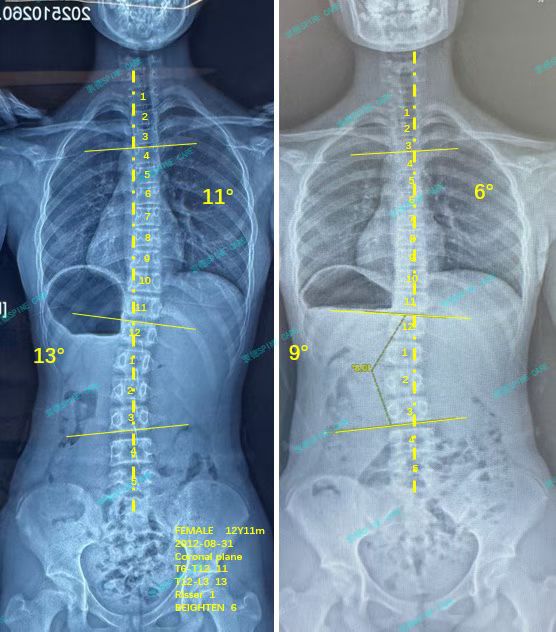

我是天天,ZDT训练3月,13度腰弯降至9度,11度胸弯降至6度,体态明显改善~

我叫天天,在衷德脊柱规律训练了三个月,我的腰弯从13度降至9度,胸弯从11度降至6度,效果很明显~

My name is Tiantian. After three months of regular spinal training at Zhongde Spine, my lumbar curvature decreased from 13 degrees to 9 degrees, and the thoracic curvature reduced from 11 degrees to 6 degrees, demonstrating significant improvement.